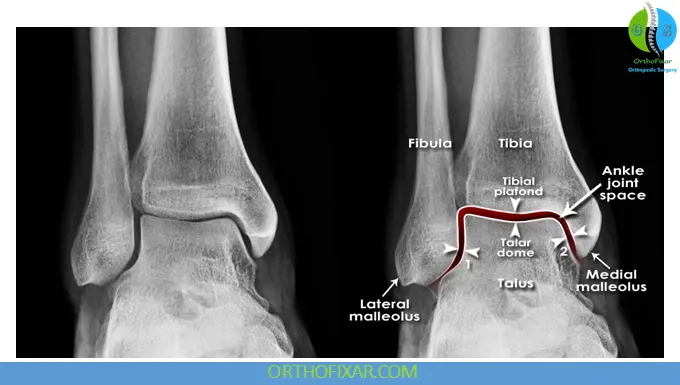

1. Anteroposterior (AP) View of the Ankle

This view demonstrates the distal tibia, fibula, ankle joint space, and talus.

There are some radiographic parameters of the ankle on anteroposterior (AP) View that should be noted in case of ankle trauma:

- The medial clear space is the space between the talus and medial malleolus. It is normally ≤ 4 mm wide, and values greater than this indicate a lateral talar shift with disruption of the ankle mortise (e.g., fibular fracture) with disruption of the deltoid and tibiofibular ligaments and, therefore, of the tibiofibular syndesmosis.

- The tibiofibular overlap or tibiofibular clear space should be at least 6 mm, and greater than 1 mm in the mortise view, although any alteration and related injury has been questioned.

- In addition, the configuration, congruity, and inclination of the talar dome in relation to the tibial vault above it should be noted, because it may indicate an osteochondral lesion or OCD.

- If epiphyseal plates are present, the examiner should note whether they appear normal. Any increase or decrease in joint space, greater reduction of the tibial overlap, widening of the interosseus space, and greater visibility of the digital fossa should also be noted.